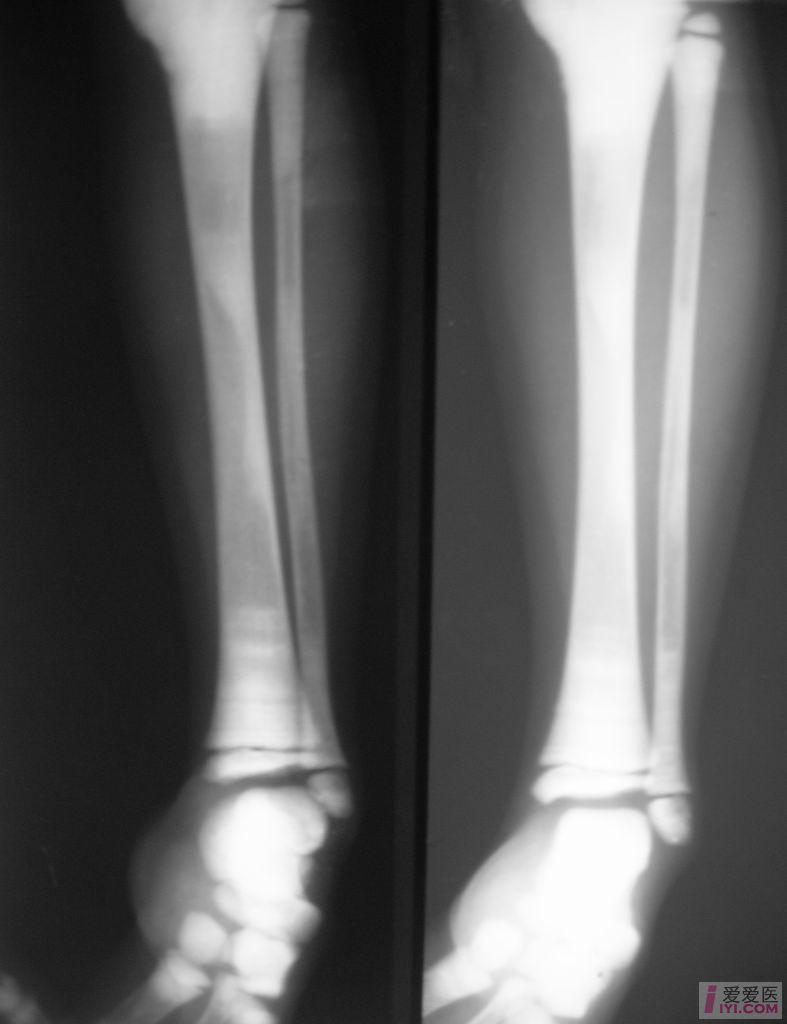

【原创】石骨症 - 医学影像学讨论版 - 爱爱医医学论坛

图片尺寸787x1024